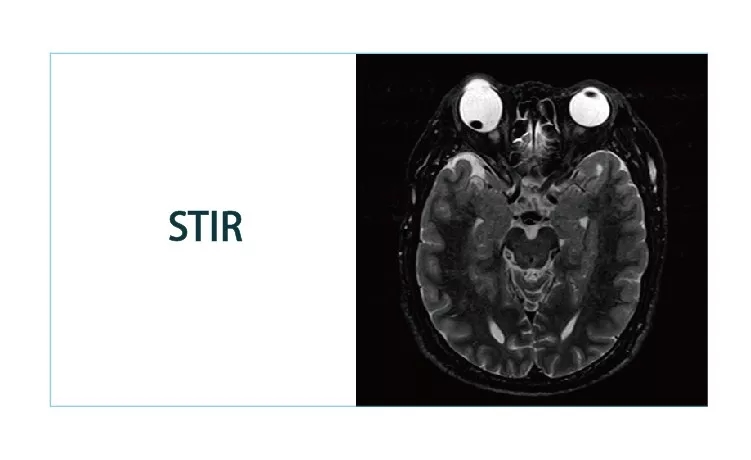

【朗润影像档案】20181214磁共振影像病例结果讨论